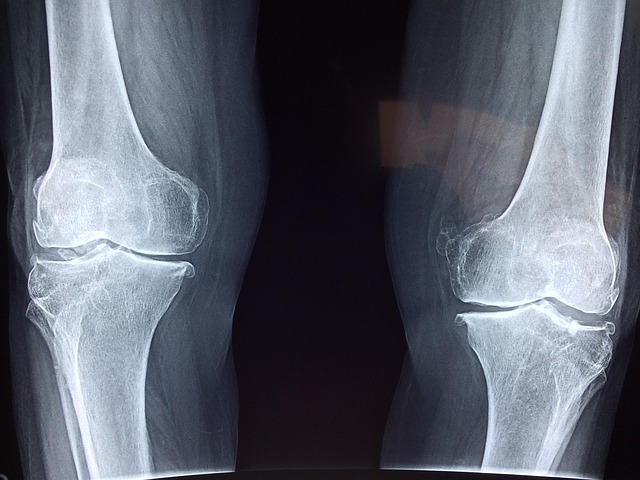

콘드로이친은 연골의 주요 구성 요소 중 하나인 글리코사미노글리칸(glycosaminoglycan)으로, 관절 건강을 유지하는 데 중요한 물질입니다. 관절 내 윤활 유체의 생성과 영양 공급에 도움을 주며, 연골 표면의 마모를 줄이고 탄력을 유지하는 데 기여합니다.

콘드로이친은 단독으로 복용되기도 하지만, 글루코사민처럼 다른 성분과 함께 복합제로 사용되기도 합니다. 이는 연골 보호 및 증상 완화 효과를 증대시키려는 목적으로 개발된 것입니다. 특히, 운동이나 일상 생활로 인해 관절에 무리가 가는 경우, 콘드로이친을 포함한 보조제를 통해 증상을 관리하려는 사람들이 많습니다.